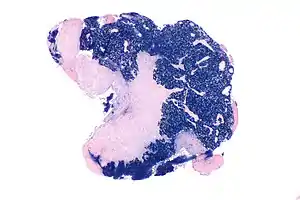

| Micrograph showing a nasopharyngeal carcinoma positive for Epstein-Barr virus-encoded small RNAs (EBER). | |

Nasopharyngeal carcinoma, also known as nasopharyngeal cancer, is classified as a malignant neoplasm, or cancer, arising from the mucosal epithelium of the nasopharynx, most often within the lateral nasopharyngeal recess or fossa of Rosenmüller (a recess behind the entrance of the eustachian tube opening). The World Health Organization classifies nasopharyngeal carcinoma in three types, in order of frequency: Non-keratinizing squamous cell carcinoma; keratinizing squamous cell carcinoma; and basaloid squamous cell carcinoma.[14] The tumor must show evidence of squamous differentiation, with the non-keratinizing type (also known as lymphoepithelioma) the tumor most strongly associated with Epstein-Barr virus infection of the cancerous cells.[15]

Undifferentiated nasopharyngeal carcinoma—low power